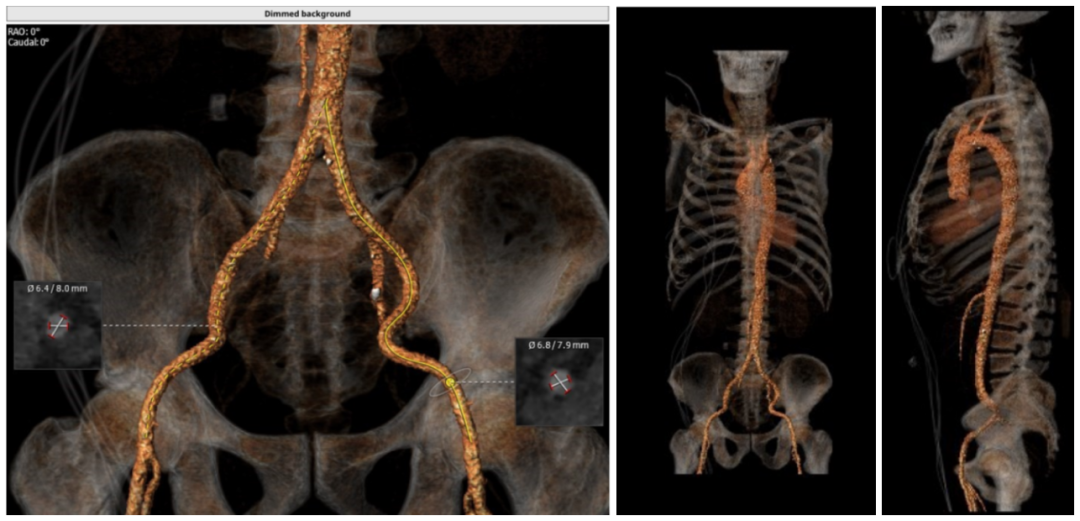

术前CT测量

瓣环:24.4mm;LVOT:22.7mm;

瓦氏窦:32.0*31.4*32.0mm;

升主动脉:32.6mm;左冠高度:17.3mm;

右冠高度:17.3mm;钙化积分:1.1mm³;

瓣环与水平面夹角:34°;

髂外动脉:6.4*8.0mm,6.8*7.9mm。

CT评估

主动脉瓣为三叶瓣,瓣叶肥厚且冗长,CT下可见少量钙化点,窦部结构和冠脉高度尚可,人工金属二尖瓣环,最高处距离主动脉瓣环6.9 mm。大血管走行自然,未见明显迂曲及钙化斑块,下肢血管内径可。